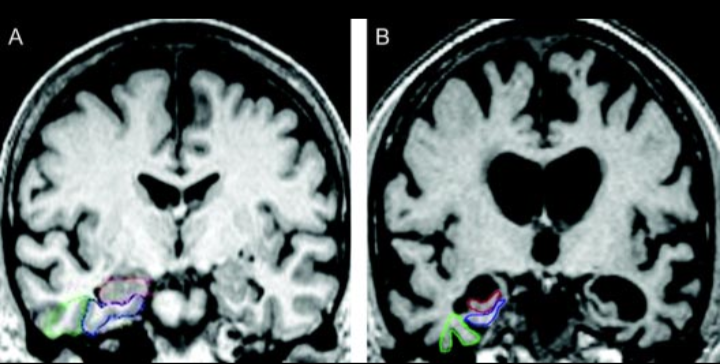

ـ أشعة الرنين المغناطيسي (MRI)

ـ فحوصات PET للكشف عن اللويحات البروتينية في الدماغ